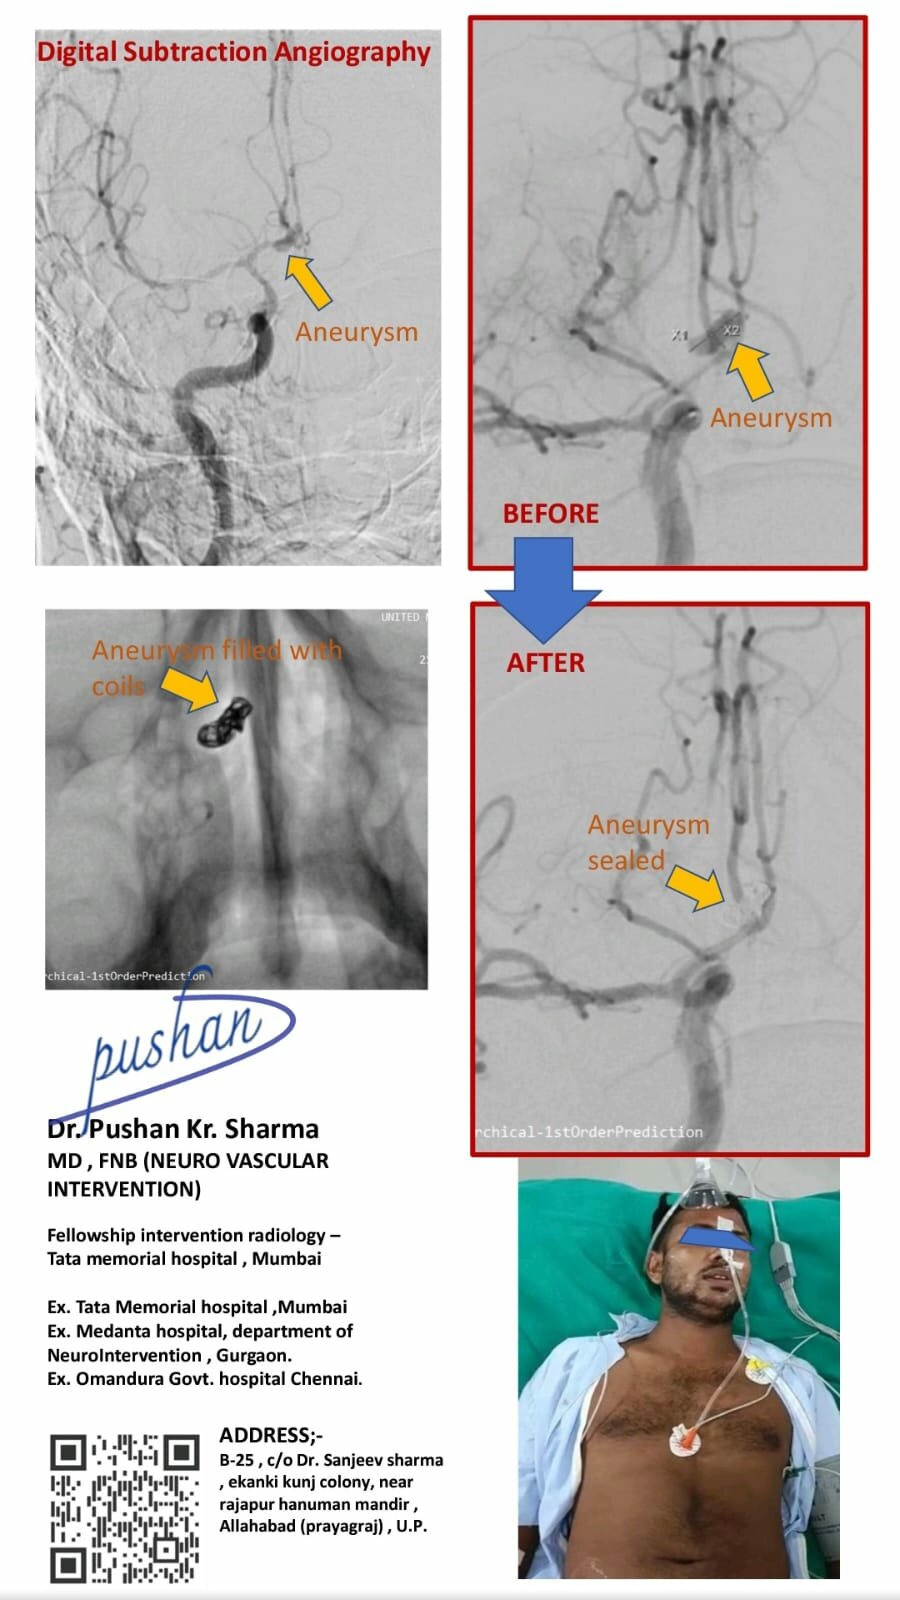

• DSA- DIGITAL SUBSTRACTION ANGIOGRAPHY

• Brain aneurysm coiling for treatment of brain hemorrhage

Dr. Pushan Sharma,MD , FNB (Neuro Vascular Intervention),Neuro and Vascular Interventional radiology

Dr. Pushan Sharma

Neuro and Vascular Interventional Radiologist

MD , FNB (Neuro Vascular Intervention)

Neuro and Vascular Interventional radiology